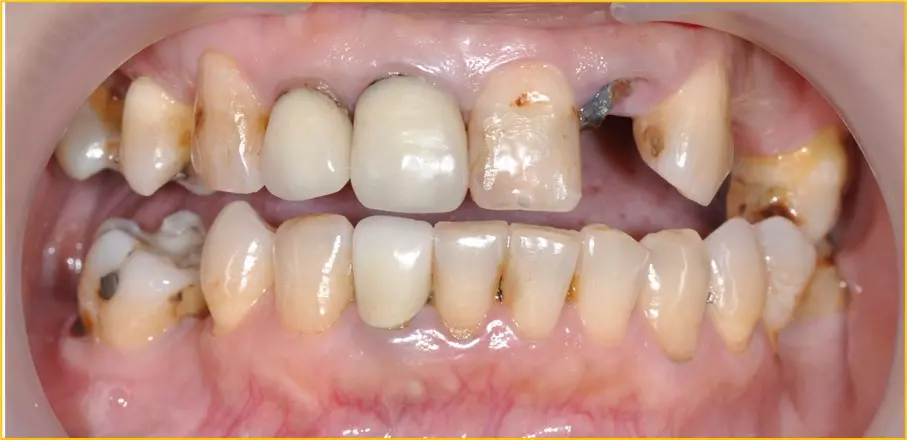

↑治療前,可以明顯看見缺牙和假牙邊緣金屬色